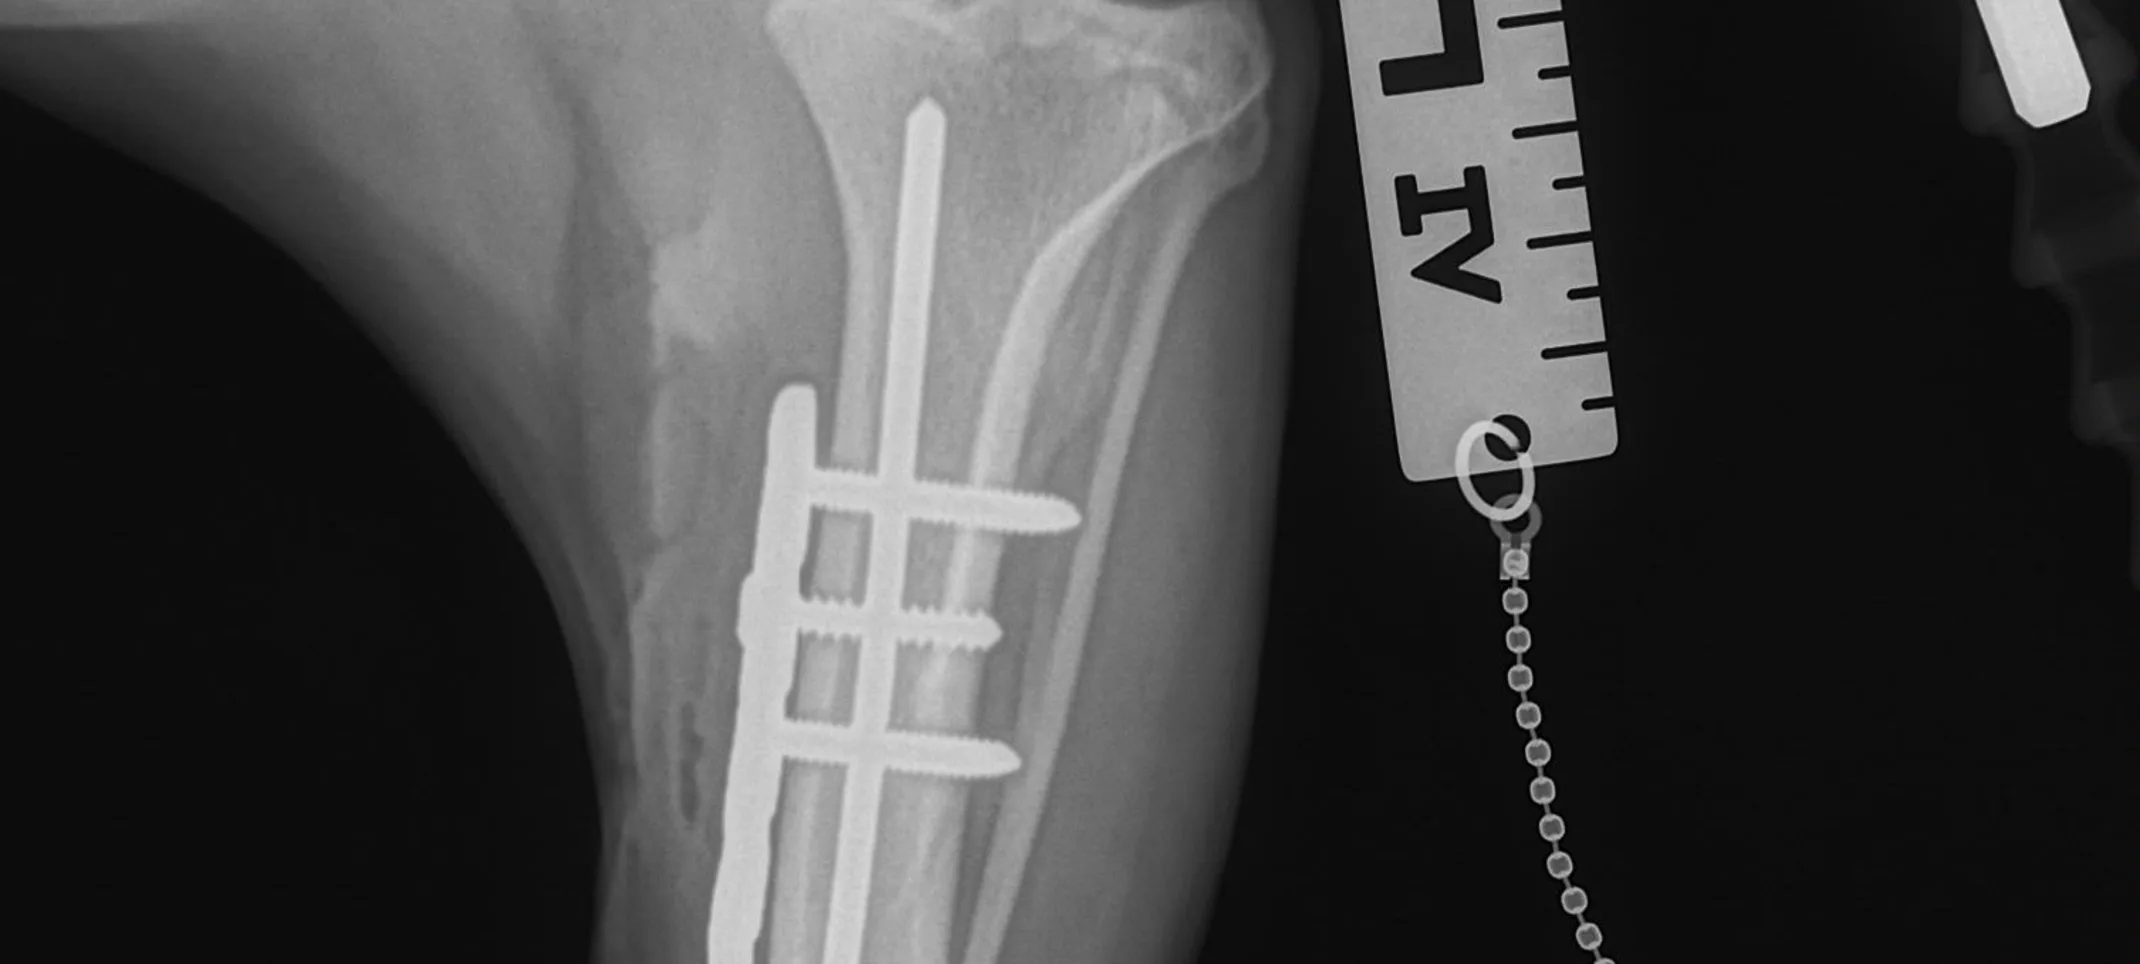

Bone Plating

Bone plating is one of the strongest and most effective methods of fixing a fracture. Fractures are common in pets and are caused by a variety of reasons.

Bone plates are strong and relatively lightweight. They counteract bending, compression, twisting and pulling forces. The plate is a custom-molded piece of steel that is screwed along the long axis of the bone, with pins that secure the plate to the bone.